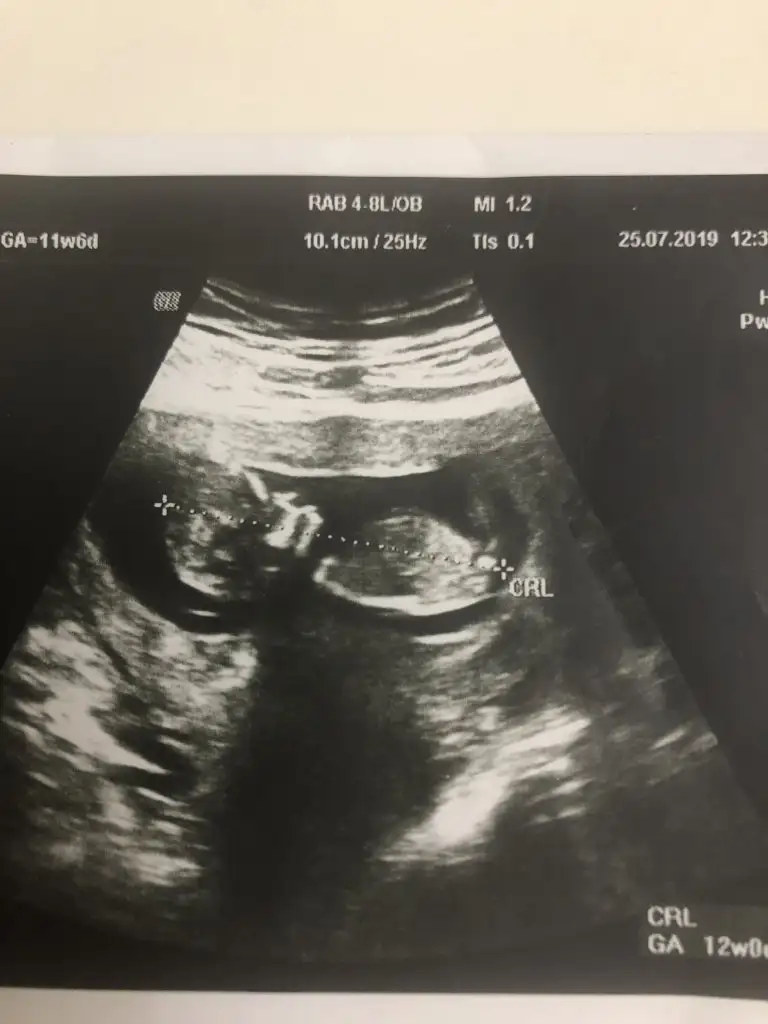

Bunlarda az önce alınan resimler normalde 11 hafta 6 günlük ama usg de 12 hafta 6 günlük

Evet gönlümden geçen erkek Bi tane kızım var çok ta sevinmiştim siz şimdi kesin kız deyince moralim bozuldu biraz. Şu an sat a göre 11 hafta 6 gün usg ye göre 12 hafta 6 gün. Doktor erkeğe çok benziyor çıkıntısı burada diyerek gösterdi kesin erkek demedi yüzde 80 erkek dedi ama bazen kızlarda da bu çıkıntı oluyor dedi. Hatta bu Nub teorisinden de bahsettim belli olmaz bazen dik bazen paralel bile olabilir dediSiz erkek istiyordunuz galiba.nub çizgisine ve kafa yapısına göre yorum yapıyorum.cinsiyet oluşmadan önce nub çizgisi oluşur.bu çizgi paralelse kız,dik ise erkek demektir.sizin bebeğinizin nub çizgisi bariz paralel.kafa yapısı da oval.erkeklerin kafa yapısı daha yuvarlak olur. Doktor kesin erkek dedi mi size? Buda cinsel organı diye gösterdi mi? Kaç haftalıksınız şuan?

Kızlarda da bu çıkıntı oluyor dediyse nub çizgisinden bahsediyor.11 12 haftada cinsel organ tam anlamıyla oluşmuyor nub çizgisi oluyor.13 14 haftalarda organ oluşmuş oluyor.yani direkt olarak pipi göstermemiş.bilmiyorum doktor erkek dediyse erkek olabilir.ben bariz kız görüyorum bu usg de.elbette doktorlar daha iyi bilir tabi.rabbim gönlünüzdekileri nasip etsin inşallah.siz sorduğunuz için cevapladım.ama bana göre bu bebiş kızEvet gönlümden geçen erkek Bi tane kızım var çok ta sevinmiştim siz şimdi kesin kız deyince moralim bozuldu biraz. Şu an sat a göre 11 hafta 6 gün usg ye göre 12 hafta 6 gün. Doktor erkeğe çok benziyor çıkıntısı burada diyerek gösterdi kesin erkek demedi yüzde 80 erkek dedi ama bazen kızlarda da bu çıkıntı oluyor dedi. Hatta bu Nub teorisinden de bahsettim belli olmaz bazen dik bazen paralel bile olabilir dedi